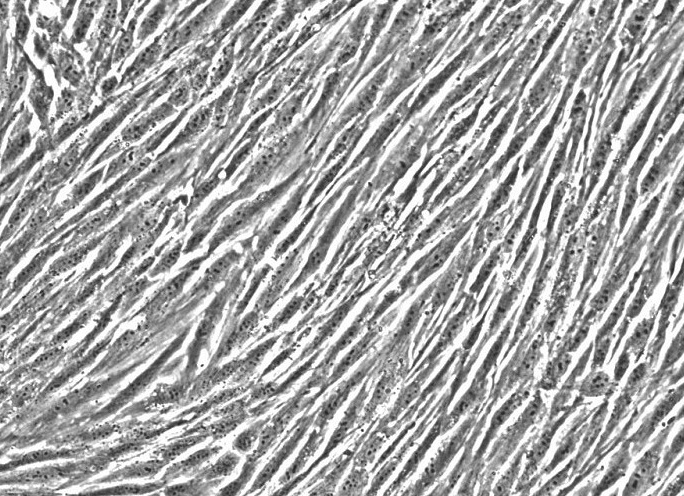

人膀胱成纤维细胞分离自正常人膀胱组织,膀胱成纤维细胞分泌的生长因子是一种具有多功能的促有丝分裂原,研究已表明其参与恶性肿瘤的形成过程。近年来,碱性成纤维细胞生长因子在膀胱癌发病过程中的作用、与生物学行为之间的关系以及治疗上的应用已受到重视。烜雅生物科技提供的人膀胱成纤维细胞均来自新鲜组织,用于培养人膀胱成纤维细胞的组织采集于地方医院,组织的采集根据美国IRB 和 HIPAA批准的方案进行。细胞的培养采用公司专利产品人膀胱成纤维细胞培养试剂盒(Human Bladder PrimaCell™: Normal Bladder Fibroblasts Cat No. 3-0281)来优化目的细胞生长条件,以降低杂细胞的污染,同时保证质量的稳定。在烜雅生物技术部标准的操作流程下,人膀胱成纤维细胞传10代以上仍可以保持原代细胞的分化状态,进而可以用于评估体外药物模型系统和调节特定基因的遗传功能。